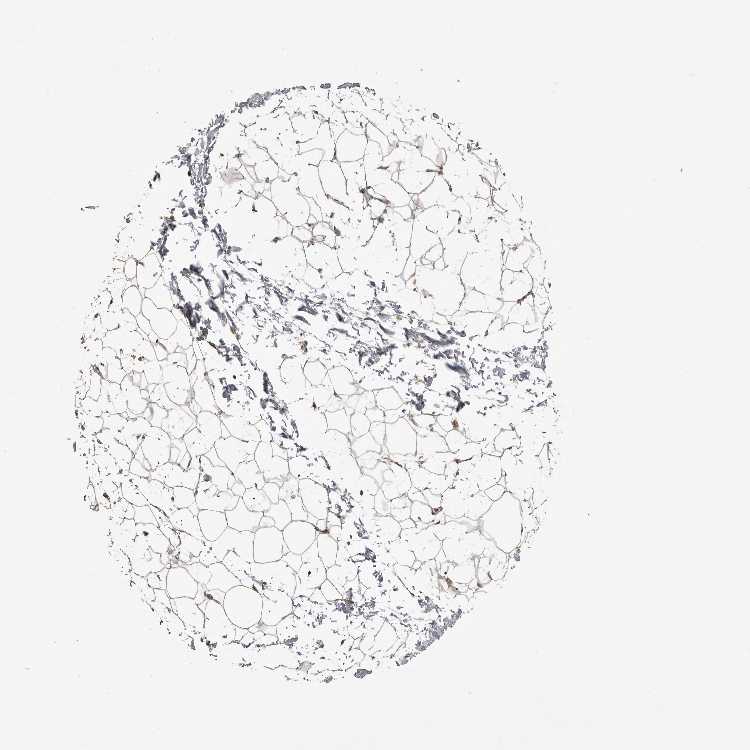

ADIPOSE TISSUE - Antibody stainingi

Antibody staining in the annotated cell types in the current human tissue is reported as not detected, low, medium, or high, based on conventional immunohistochemistry profiling in selected tissues. This score is based on the combination of the staining intensity and fraction of stained cells. Each image is clickable and will lead to virtual microscopy that enables deeper exploration of all samples and also displays staining intensity scores, fraction scores and subcellular localization as well as patient and tissue information for each sample.

Antibody HPA026980

Adipocytes Low